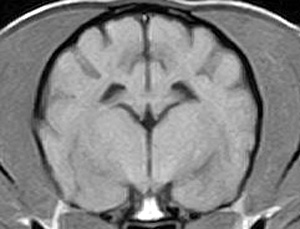

市内の先生からけいれん発作が出るとのことでMRI検査のご依頼がありました。検査では脳に構造上の異常を認めず、脳脊髄液検査も問題なく、特発性てんかんとの診断でご紹介もとの病院様での治療となりました。